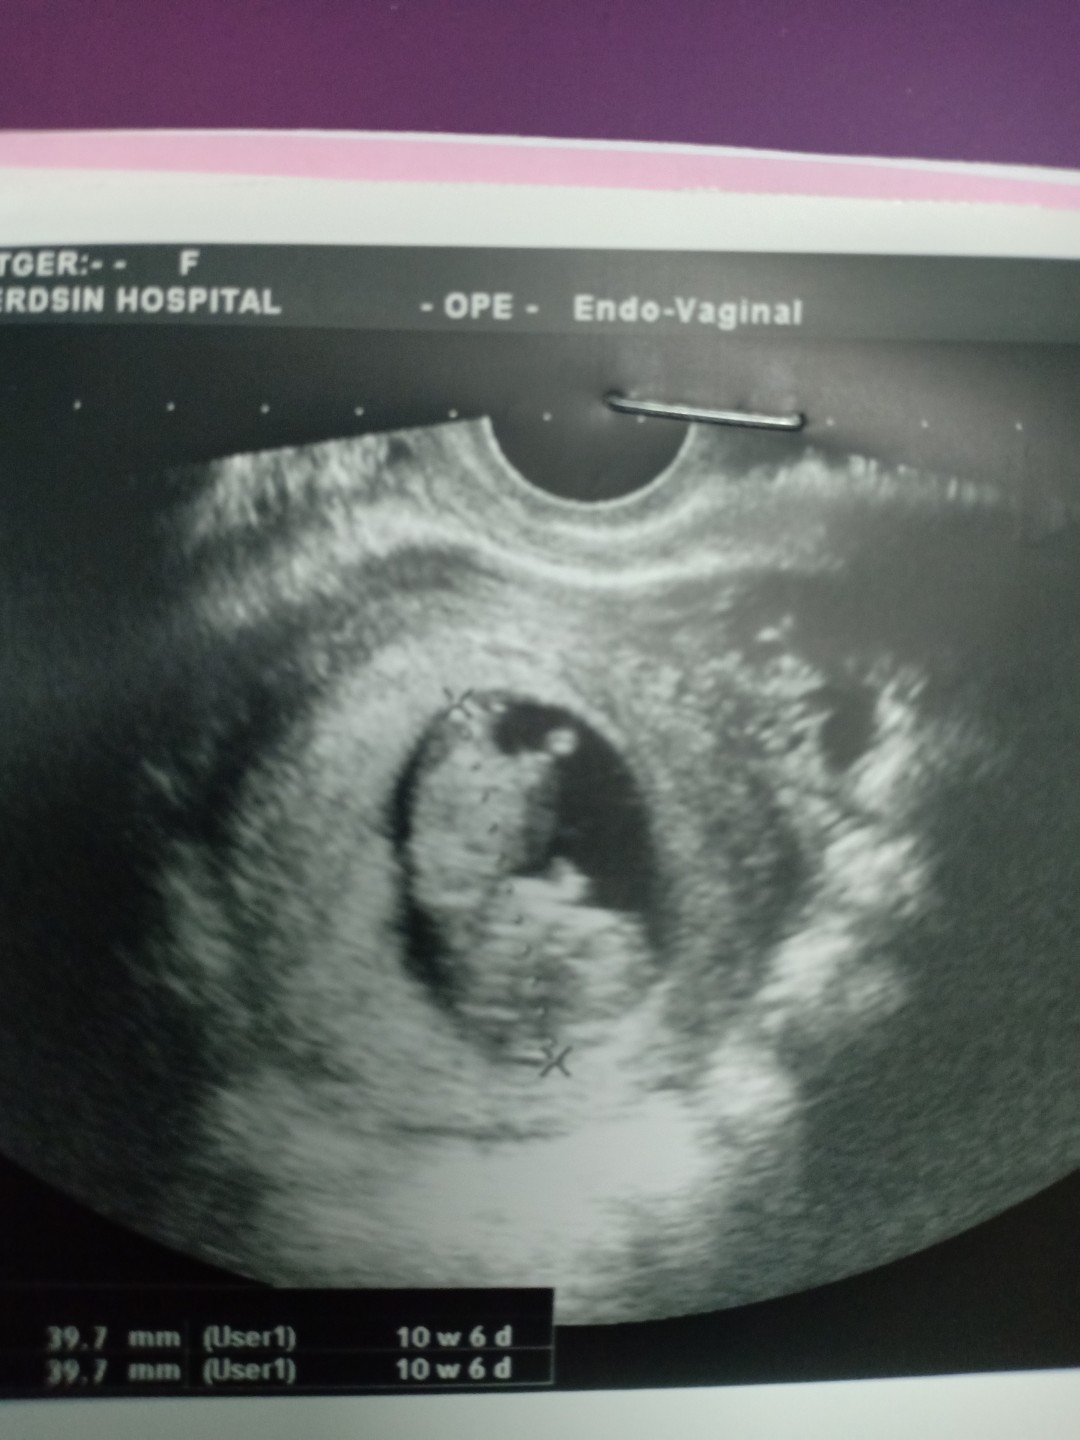

ใครอัลตร้าซาวด์เป็นแบบนี้บ้างค่ะ

คือคุณหมอเขาสันนิฐานว่าน่าจะท้องถุงลม กับท้องแต่น้องตัวเล็กเกิน #ท้อง3เดือน

อันนี้ของเราตอน10wคะ